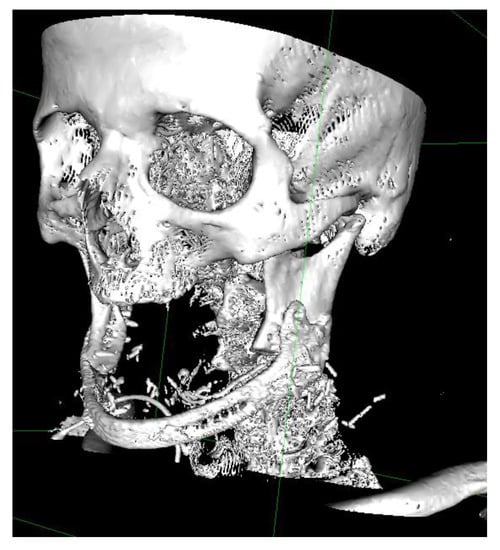

2.1. Protocol for Computer-Assisted Design and Manufacturing Bridging Plate

2.2. Surgical Procedure